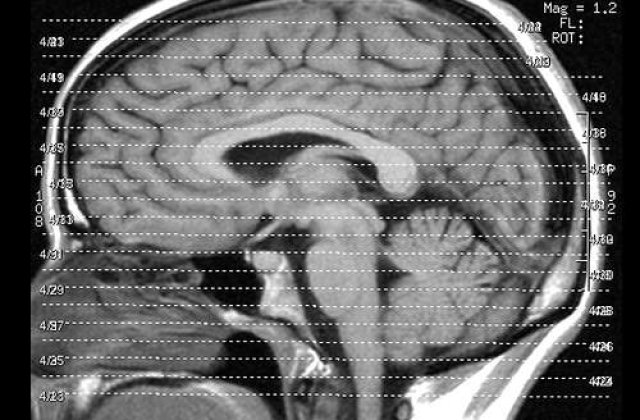

Putem reusi orice daca vrem cu adevarat, fara sa ne plangem ca "X" s-a nascut mai destept decat noi. In plus, nu trebuie sa uitam ca creierul este organul cel mai pretios pentru intreg organismul. Daca il facem pe el sa se simta mai bine, vom duce categoric o viata mult mai sanatoasa.